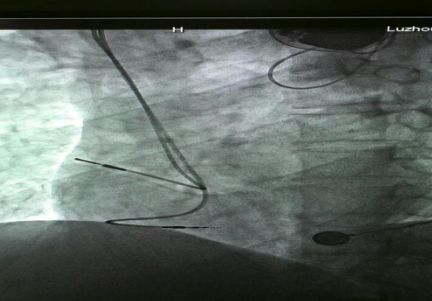

已安裝好的起搏系統(tǒng)

在征得患者及家屬的同意后,我院為其實(shí)施了雙腔永久心臟起搏器植入術(shù),該手術(shù)在瀘州市市屬醫(yī)院中率先使用磁共振兼容起搏電極,為患者未來有可能接受的磁共振檢查創(chuàng)造了條件。